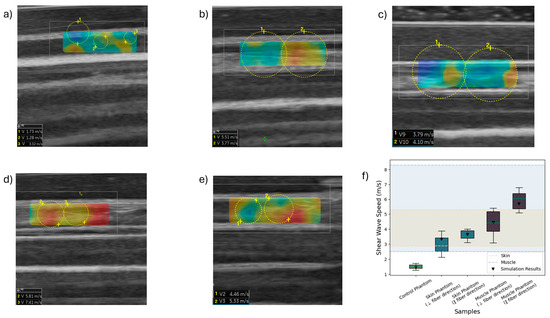

Figure 10 clearly demonstrates distinct SWS variations among the three phantom types tested. The observed differences indicate the successful tuning of phantom stiffness and anisotropic properties, intended to mimic biological tissue characteristics.

The ultrasound imaging clearly revealed differences in the structural composition of the evaluated phantom samples. The control phantom (Figure 10a) exhibited uniform ultrasound characteristics with a homogeneous and isotropic silicone structure, indicating no observable internal fiber reinforcement or anisotropic structures.

In contrast, the laminated skin phantom (Figure 10b,c), distinctly showed two separate layers: the upper layer composed exclusively of silicone, appearing uniform and homogeneous, and the bottom layer containing natural fibers dispersed within the silicone matrix. This structural difference was directly observable, providing clear confirmation of successful fabrication and layer differentiation. When the ultrasound beam traversed the sample parallel to the fiber orientation, a significant increase in shear wave velocity was consistently observed compared with the silicone-only layer, and the architecture of the fibers was clearly visible in the ultrasound images (Figure 10b), reaching an SWS of 2.98 ± 0.72 m/s. Notably, when the beam orientation was perpendicular to the fiber direction, a reduction in shear wave velocity was observed, highlighting the anisotropic nature imparted by the fibers (Figure 10c), reaching an SWS of 3.58 ± 0.33 m/s. This phenomenon highlights the crucial role of natural fibers, acting both as structural reinforcement and as agents that alter and disperse mechanical waves, thus increasing overall shear wave speed.

The muscle phantom (Figure 10d,e) revealed distinct anisotropic behavior characterized by a heterogeneous ultrasound image due to fiber alignment and density variations within the silicone matrix. Ultrasound measurements demonstrated considerable variation in shear wave velocities dependent on fiber orientation relative to the ultrasound beam. When the beam was parallel to the fibers, higher velocities were observed, and the clear visibility of fibers was similar to the ultrasound appearance of skeletal muscle (Figure 10d), reaching an SWS of 4.43 ± 0.74 m/s. Conversely, when the beam was perpendicular to the fiber direction, ultrasound images showed less distinct fiber architecture and a decrease in shear wave velocities (Figure 10e), reaching an SWS of 5.93 ± 0.62 m/s.

This anisotropic contrast further confirmed the fibers’ reinforcing and wave-dispersing roles, effectively mimicking the mechanical behavior typical of skeletal muscle tissue. The use of ultrasound coupling gel between the layers additionally created imaging characteristics resembling adipose tissue, further enhancing the biological realism of the phantom.

These findings emphasize the dual functionality of fibers in composite phantom design. By acting simultaneously as reinforcing elements and wave-dispersing agents, fibers enhance the mechanical integrity of the phantoms and replicate the anisotropic wave propagation behaviors observed in biological tissues. This dual role reinforces the suitability of natural fiber–elastomer composites as versatile, tunable, and biologically representative ultrasound medical phantoms.

Regarding the SWSs observed, starting with the control phantom (1.5 ± 0.22 m/s), these were relatively low, consistently falling below 2 m/s, indicating that this material presented properties typical of soft, isotropic silicone without fiber reinforcement. This is in line with expectations, as control phantoms typically aim to represent baseline isotropic and softer properties compared with biologically anisotropic tissues. The simulation result for the same phantom, which yielded a shear wave speed of 1.46 m/s, closely aligns with the experimental measurements, further validating the accuracy of the simulation approach and the chosen material parameters for modeling the silicone matrix.

In contrast, the skin phantom demonstrated SWSs within the range of 3.65 ± 0.51 m/s. This closely matches the reported stiffness of human skin tissue, as depicted by the highlighted region labeled “Skin” in the graph (2.87–5.31 m/s [75]). The relatively narrow dispersion of SWS values indicates uniform stiffness and the successful tuning of the phantom to represent human skin elasticity. This alignment suggests the appropriateness of the phantom composition and fiber reinforcement approach to mimic human skin effectively. Additionally, the simulation of this sample yielded a shear wave speed of 3.74 m/s, which is in strong agreement with experimental results and further supports the validity of the model assumptions and the mechanical characterization of the composite.

The muscle phantom presented a broader variability in SWS, with values of 5.93 ± 0.62 m/s, thus spanning the range reported in the literature for human skeletal muscle tissue, highlighted as “Muscle” in the graph (2.5–8.3 m/s [76]). The increased variability is likely related to the anisotropic nature of muscle, in which fiber orientation significantly influences elastic properties. Therefore, measuring parallelly and perpendicularly to the fiber orientation could contribute significantly to this observed dispersion. This finding reinforces that the phantom structure successfully emulated the anisotropic behavior characteristic of skeletal muscle. Furthermore, the simulation of the muscle phantom yielded a shear wave speed of 5.44 m/s, which falls within the experimental range and further supports the model’s capability to reproduce both the magnitude and variability of wave propagation in anisotropic composite structures.